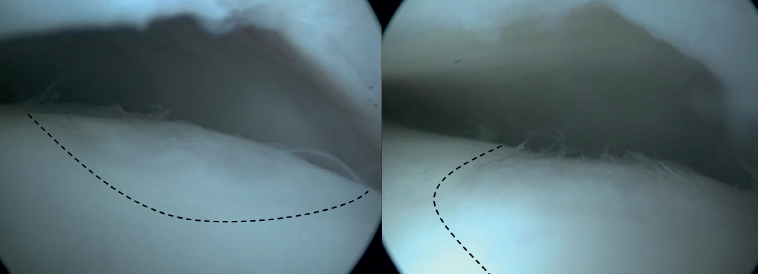

La estimulación de la médula ósea (EMO) por artroscopia es el tratamiento más frecuentemente utilizado para la lesión osteocondral primaria del astrágalo(22). Es posible utilizar la EMO en lesiones relativamente pequeñas (< 15 mm), no quísticas y no fijables(20,23). La EMO por artroscopia comienza con el desbridamiento y curetaje del cartílago defectuoso y del hueso subcondral(24). Posteriormente, se perfora el hueso esclerótico a la altura de la base del defecto, a menudo con una aguja de Kirschner o un punzón para microfractura(25). Los orificios deben realizarse a una profundidad que provoque la hemorragia del hueso subcondral o la presencia de gotas de grasa(23) (Figura 4). Esta técnica interrumpe los vasos sanguíneos intraóseos, lo que provoca la hemorragia del hueso subcondral y la formación de un coágulo de fibrina. La liberación de células sanguíneas mesenquimales favorece la vascularización, lo que induce la formación de fibrocartílago(26). Cuando se trata de una lesión cartilaginosa aislada (es decir, sin otras lesiones óseas o articulares) con una capa ósea subcondral macroscópicamente intacta, solo puede realizarse un desbridamiento(27).